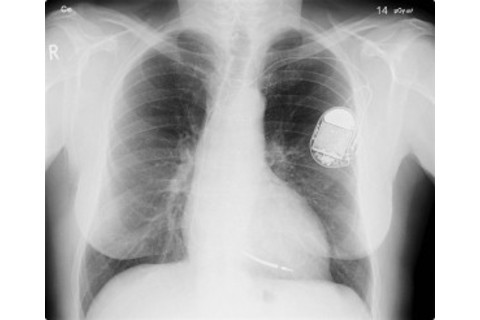

Many implants like this pacemaker can receive and transmit wireless signals

The Future Holds: Such attacks haven't happened yet, to our knowledge. But given the risks---disclosure of patient's names and medical data, and potentially fatal interference---it behooves medical device companies to start looking into solutions like the shield. Image credit: Wikimedia Commons